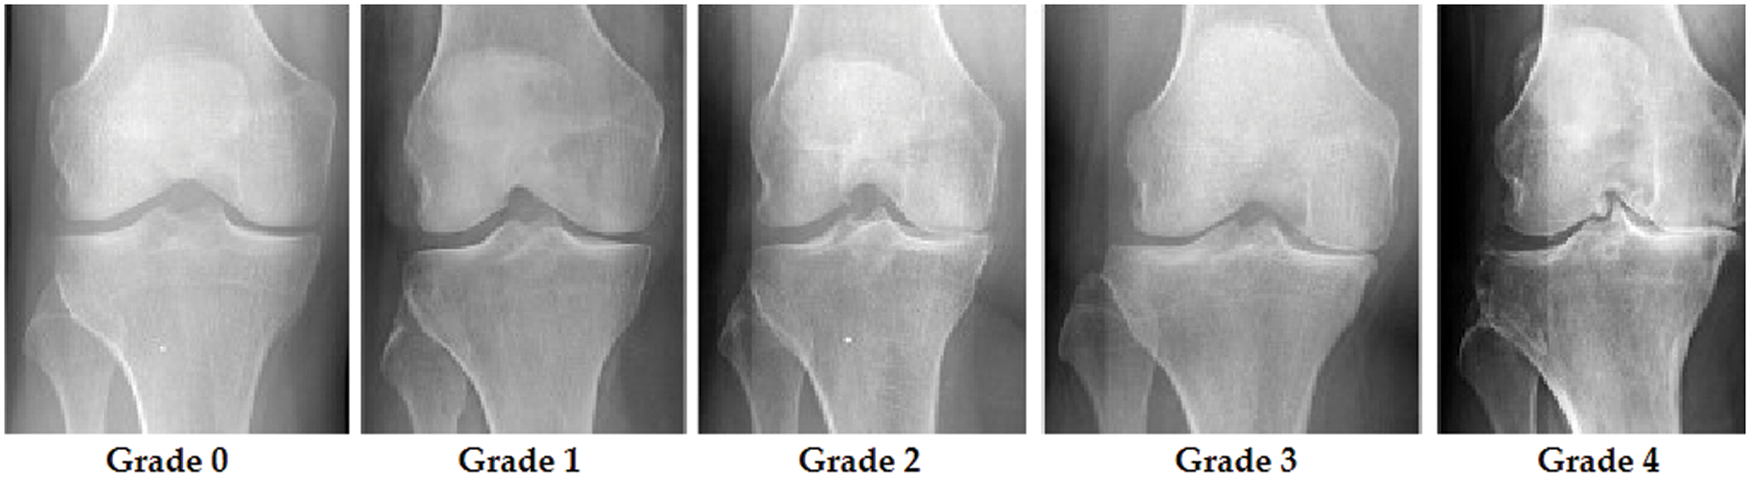

Grade 0 indicates healthy joints where the radiological characteristics of knee osteoarthritis are absent. Grade 1 KOA indicates the likelihood of osteophytic lip and dubious JSN. Grade 2 OA is characterized by the existence of osteophytes and the potential of JSN [9]. The presence of JSN, numerous osteophytes, and sclerosis characterizes grade 3 OA. Finally, grade 4 indicates severe OA due to massive osteophytes within the joints, as shown by JSN and extensive sclerosis. Fig. 2 depicts knee joint specimens from each KL grade.

Figure 2: KOA levels according to KL grades